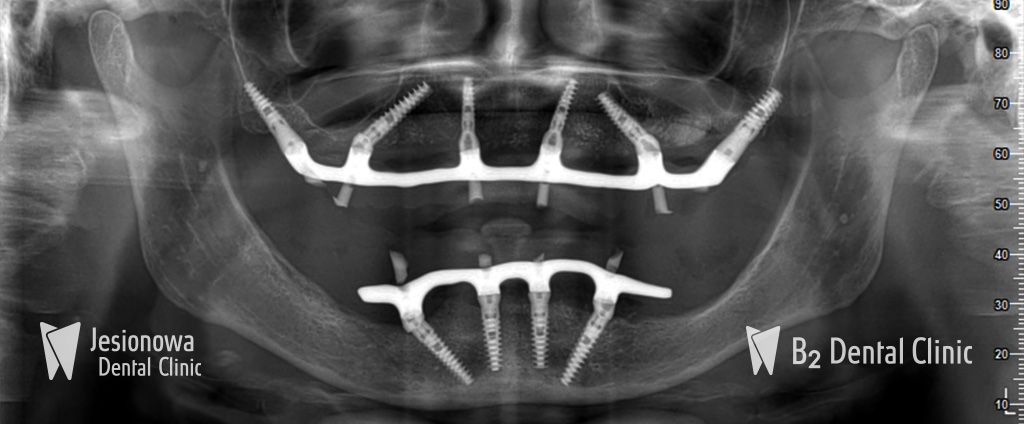

All-on-6 to metoda leczenia bezzębia polegająca na zastąpieniu brakujących zębów przy użyciu pojedynczego mostu mocowanego na stałe, obejmującego cały łuk zębowy przy użyciu 6 implantów zębowych i natychmiastowego ich obciążenia.

Metoda All-on-6 wymaga zastosowania jedynie 6 implantów w celu zastąpienia 14 zębów. Wprowadzenie 6 implantów w szczęce zapewnia optymalne koszty oraz przewidywalność leczenia.

Zabieg podnoszenia zatok szczękowych przy zastosowaniu metody All-on-6 nie jest konieczny. Specjalne pochylenie 4 implantów zapewnia odpowiednią stabilizację w łuku zębowym oraz ominięcie zatok szczękowych.

3. Wszczepienie implantów i praca protetyczna

Na tym etapie wszczepiamy 6 implantów do których zostanie przymocowana stała praca protetyczna. Zabieg jest całkowicie bezbolesny, a jego czas trwania wynosi średnio 90 min (bez dodatkowych zabiegów regeneracyjnych kości).